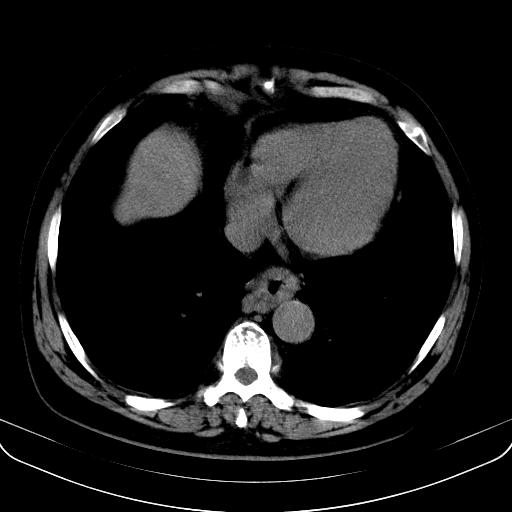

以下是引用jia119在2008-3-5 13:31:00的发言:[br]肝内多发片状低密度影,密度不均,我还是考虑肝ca可能,另肝内小囊肿,胆囊增大。

以下是引用形影不离在2008-3-5 12:18:00的发言:[br]肝硬化伴门脉高压征,肝内占位待排,增强再说.

以下是引用随光逐影在2008-3-5 21:11:00的发言:[br]肝硬化伴门脉高压(食管下段静脉曲张),肝癌不排除。建议:行ct增强扫描检查。

以下是引用同在2008-3-5 13:56:00的发言:[br]考虑肝癌可能性大,胆囊增大.